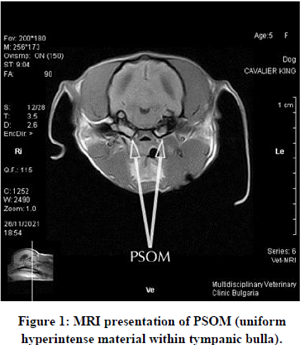

Primary secretory otitis media (PSOM) -- also known as "glue ear" or "middle ear effusion" (MEE) or "otitis media with effusion" (OME) -- is frequently diagnosed in cavalier King Charles spaniels. It is an inflammation of the dog's middle ear which consists of a highly viscous mucus plug which fills the middle ear cavity and may cause the tympanic membrane to bulge. The mucus has also been referred to as "hyperintense material".

PSOM may be detected by veterinary neurology or dermatology specialists from either magnetic resonance imaging (MRI) or a computed tomography (CT) scan. Both require that the dog be under general anesthesia. It also may be observed using an operating microscope with good lighting and at a suitable magnification.

Diagnostic imaging by magnetic resonance imaging (MRI) scan is another option, however it is much more expensive than otocsopy and CT scans and also requires general anesethesia. CT usually is the preferred method because it is more sensitive and specific for changes to the middle ear's bony structures. In the MRI image at the right (courtesy, Downs Veterinary Practice, Bristol, UK.), the two bowl-shaped bullae are shown to contain accumulated mucus.

March 2023 article, Bulgarian clinician Ivelina Vacheva (right)

MRI (which she described as “a crucial part of PSOM diagnosis);

MRI (which she described as “a crucial part of PSOM diagnosis);